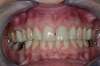

Qualité de la gencive et intégration a 15 jours.

Qualité des tissus mous après un an.